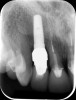

Fig 1. Clinical photograph showing significant issues related to implant midfacial mucosal recession and loss of interdental papillae. This is attributed to incorrect implant positioning (too buccal and too deep); several corrective surgeries resulted in interproximal bone loss, then loss of interdental papillae.

Figure 1

A minimum of 2 mm of facial bone thickness has been proposed as the “critical bone thickness” for the prevention of vertical height loss of the facial plate. It has been reported that when the distance of the buccal shoulder position of the implant to facial bone plate is below this critical thickness, an increased amount of facial bone resorption may be observed, which, in turn, may increase the chance of implant mucosal recession and failure (Figure 1). When the facial bone thickness is more than 2 mm from the implant buccal shoulder position, the likelihood of facial bone loss is decreased and the chance for alveolar bone stability is, therefore, increased.16

Chen and coworkers evaluated the soft-tissue and radiographic outcomes of implants placed in extraction sockets using a nonsubmerged protocol. The result showed statistically significantly higher marginal tissue recession at sites when implants were placed 1.1 mm from the inner buccal socket wall compared with implants placed 2.3 mm from the inner buccal socket wall. Six of the eight implant cases that were buccally positioned had unsatisfactory post-restorative esthetic outcomes. The authors concluded that position of the implant shoulder within the socket is a critical factor for ideal esthetic outcomes; thus, a minimum of 2 mm distance from the implant shoulder to the inner buccal shoulder wall was recommended to prevent implant marginal tissue recession.5